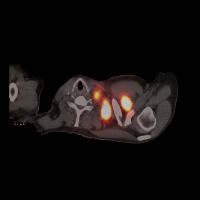

Diagnostic Aid in Medical Imaging: Radiologists could use this model to identify and characterize lymph node tumors in CT scans, assisting in early detection and diagnosis of potential cancerous growths.

Medical Research: Researchers might employ the model to study the characteristics and progressions of various types of lymph node tumors, towards producing more effective treatments and prevention strategies.

Training Medical Students: This model could serve as an invaluable tool for training medical students or residents in radiology, allowing them to familiarize themselves with the appearance and location of different lymph nodes, as well as to recognize varied tumor classifications.

Telemedicine: In remote or rural areas lacking immediate access to expert radiologists, this model can come handy as it assists primary care providers or mid-level practitioners in identifying lymph node tumors and making more effective referrals.

Second Opinion: Patients with possible lymph node tumors might use the model as a 'second opinion' to verify diagnoses, ensuring there are no oversights in their scans.